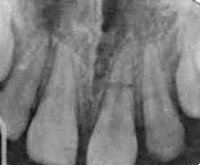

• Поперечные. Линия разлома проходит параллельно жевательной поверхности. На рентгенограмме удается рассмотреть 1-2 полоски просветления, соответствующие уровню повреждения.

При косых медио-дистальных переломах корня зуба, а также в случае, когда линии перелома перпендикулярны рентгеновскому лучу, обнаружить разлом корня с помощью прицельной рентгенологической диагностики довольно сложно. Для уточнения характера патологии проводят КТ. При горизонтальных, вертикальных вестибуло-оральных переломах корня зуба на рентгенограммах выявляют расширение периодонтальной щели. Зона разрежения костной ткани в виде тонкой полоски просветления проходит в участке повреждения. При позднем обращении пациентов рентгенографически в проекции перелома корня зуба определяют участок деструкции кости с нечеткими контурами, наблюдаются признаки резорбции корня. Прицельную рентгенографию проводят дважды: в момент травмы и через неделю.